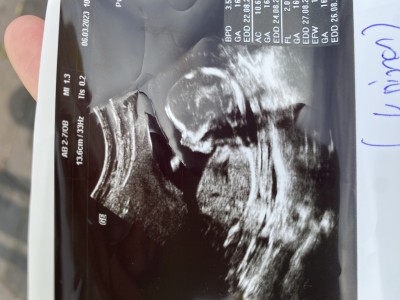

Merhaba hanımlar benim bebişim için de tahminde bulunur musunuz Rica etsek ☺️

Yüzde yüz erkek diyorum crl yaziyo ya orda o düşük olunca erkek kız olunca yüksek çıkıyormuş en son gebeligimde de düşüktü bebeğim erkekti

Bana kizdilar ama bak ikinc alttaki resimde bebisin karninin altina dogru yavasca bak ve orda iki küçük çıkıntı var canim be orda gördüm oyuzden dedim yinede tahmindi ama sevindim

Erkek gibi 15+5 demişsin fotoda 12 +4, yazıyor

İkisi de farklı fotoğraf biri 12+4 ait biri de 15+5 birinden anlaşılmazsa ötekinden belki anlaşılır diye koydum ikisinide